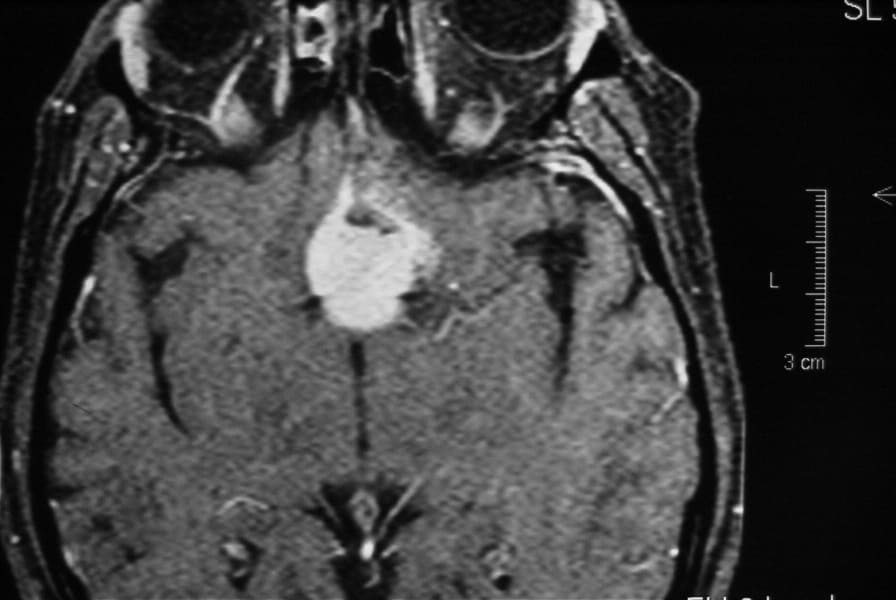

• RM cerebral